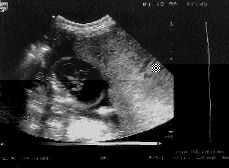

En la consulta de urgencias durante la exploración clínica nos llamó la atención una tensión arterial de 130/90, una anemia materna moderada y una altura uterina de 30 cm (10 cm más de lo que le correspondería). Sin embargo, la ecografía obstétrica visualizaba un feto con un diámetro biparietal y longitud correspondientes al tiempo de amenorrea, pero con ascitis marcada (+++) (Fig. 1), edema cutáneo (++) y una malformación cardíaca severa difícil de determinar (compatible con transposición de grandes vasos o tetralogía de Fallop) (4). Asimismo presentaba un derrame pericárdico, pleural y CIR asimétrico (5). A nivel placentario, un gran edema con áreas econegativas y un grosor máximo de 105 mm (Fig. 2). La localización placentaria era en cara anterior uterina.

Figura 1.Ascitis marcada en hydrops fetalis.

Figura 2.Engrosamiento placentario sin áreas sonoluscentes. Feto con ascitis marcada.